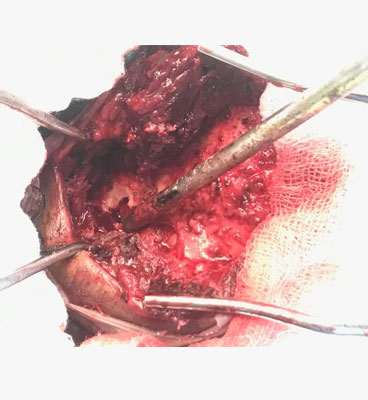

Dr. Ujwal Yeole is an experienced neurosurgeon specializes in treating a wide spectrum of neurological conditions including neuro-oncology, peripheral nerve disorders, vascular disorders, spinal pathologies, pediatric neurosurgery, neuro-trauma and skull base neuroendoscopic procedures.